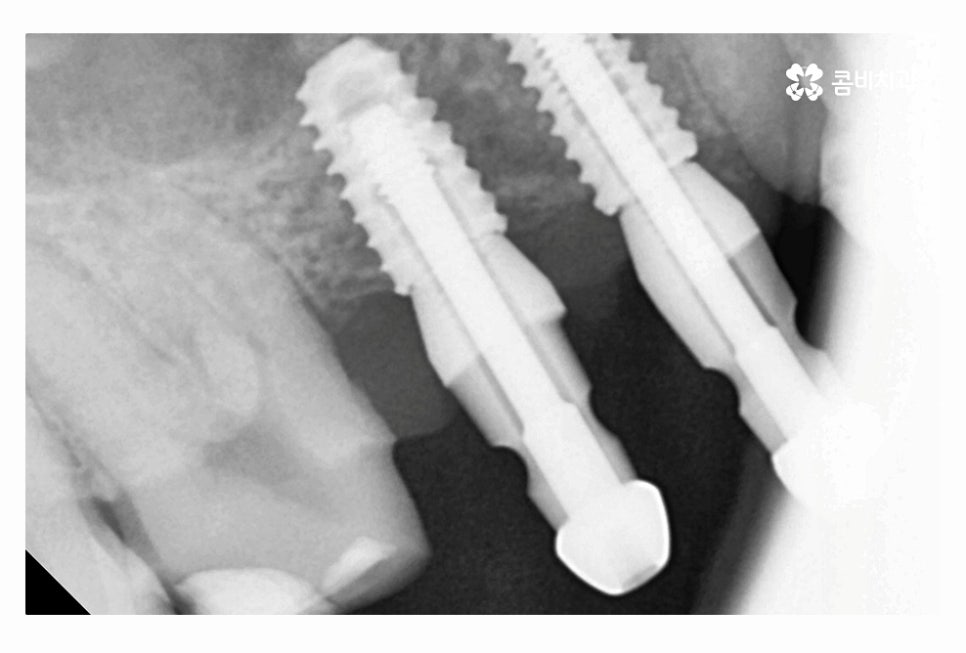

임플란트의 원리는 잇몸에 임플란트를 식립하고 골유착 과정을 통해서

단단하게 인공치근이 고정이 되고 보철물을 연결하여

자연치아의 기능 거의 대부분을 회복할 수 있는데요.

특히 20대임플란트 치료를 하시는 분들의 경우 앞으로 되도록

오랜 기간 건강하게 임플란트 수명을 유지해야 하며

부작용에 주의해야 하기 때문에 오랫동안 믿고 찾을 치과의 선택이 중요할 수 있어요.

그리고 임플란트의 재료도 수명 관리에 중요하니 단지 저렴한 곳을

선택하는 것이 아니라 장기적인 관점으로 하나하나 철저하게 따져보실 필요가 있는데요.